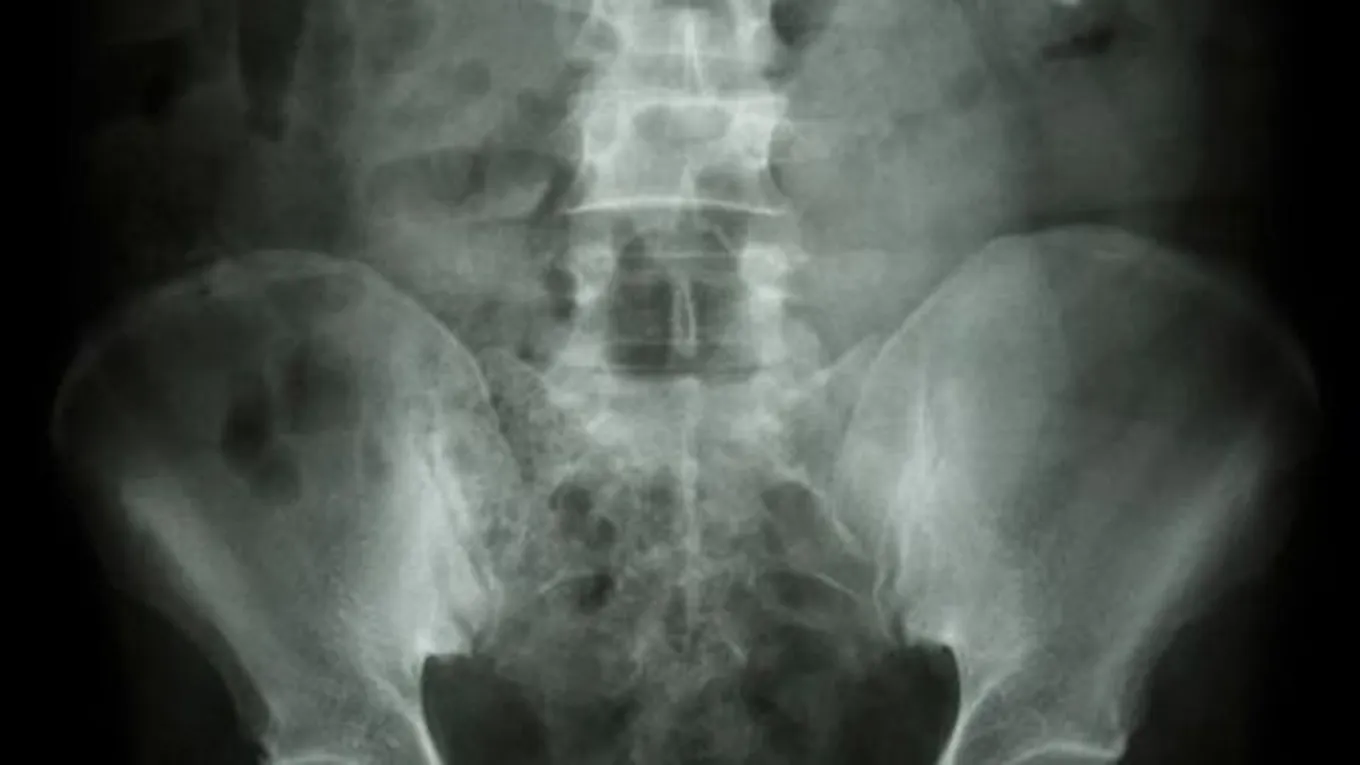

- تكلّس الكلى: قد يؤدي حدوث التكلّس في الكلى إلى المُعاناة من تشكّل حصى الكِلى.

- تكلّس الكلى: يُساهم علاج حصى الكلى في تفتيت الكالسيوم المُتراكم في الكليتين، وقد يصِف الطبيب مدرّات البول من نوع الثيازيد (بالإنجليزية: Thiazide) للحدّ من تشكّل حصوات الكالسيوم في الكِلى مستقبلاً.[4]